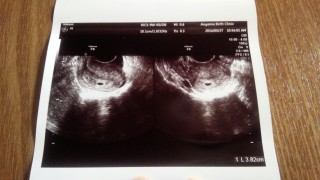

3人目の妊娠です!上が5歳、下が1歳です。下の子がなかなかできず、治療しやっと授かった子でした。しかし今回自然妊娠し、驚きとともに喜びでいっぱいですo(^▽^)o 妊娠の知識も多少あるので、今回初めての検診で5mmの胎嚢が少し小さいなーっと感じ不安になっています。 でも、わたしはこの子を信じます。 パパもママもお兄ちゃんたちもあなたに会える日を待ち望んでいるよ!元気に産まれておいで!

生理不順なのでハッキリはわかりませんが、二回目の検診で7mmの胎嚢発見‼︎